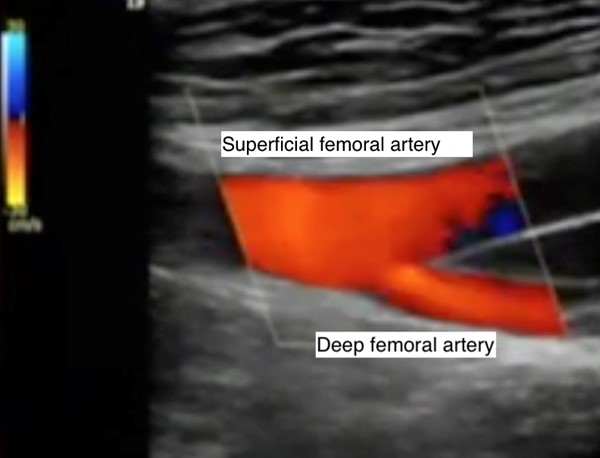

Femoral and popliteal pulses should be checked to assess for more proximal arterial disease (Figures 5 and 6).[43] Auscultate femoral/popliteal arteries for bruits.[3]

|

Fig. 5. Palpate the femoral pulse right below the groin crease, at the midinguinal point

Fig. 6. Palpate the popliteal pulse by pressing deeply into the popliteal space of a completely relaxed leg